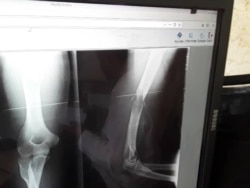

"El día 31 de octubre, la silla de ruedas que él utiliza se la dieron a otro preso", lo que obligó a Pérez Carmenate a permanecer en cama. Además de esto, el brazo operado el 17 de octubre no recibió curas, ni le fue cambiada la venda pese a la suciedad", detalló la madre del reo.

El activista, que cumple una condena de un año y cuatro meses por el delito de desobediencia, fue golpeado en plena calle el 12 de agosto pasado por agentes de la policía.

Pérez Carmenate permaneció 40 días sin asistencia médica en prisión hasta que fue operado de la lesión en un brazo, el 8 de octubre, en el hospital Clínico Quirúrgico de Las Tunas, y luego regresado a prisión.